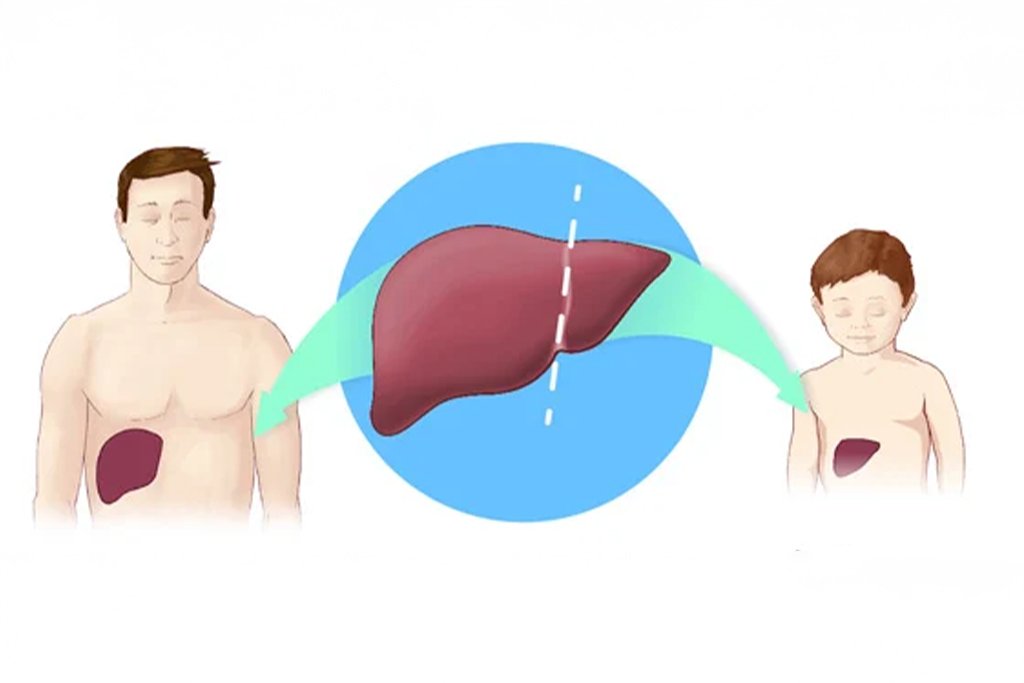

Split Liver Transplant

- A single donor liver is split into two sections to save two patients, usually an adult and a child

Living Donor Liver Transplant (LDLT)

- Involves transplanting a portion of the liver from a healthy living donor (usually a close family member).

- The donor’s liver regenerates over time, restoring full function.